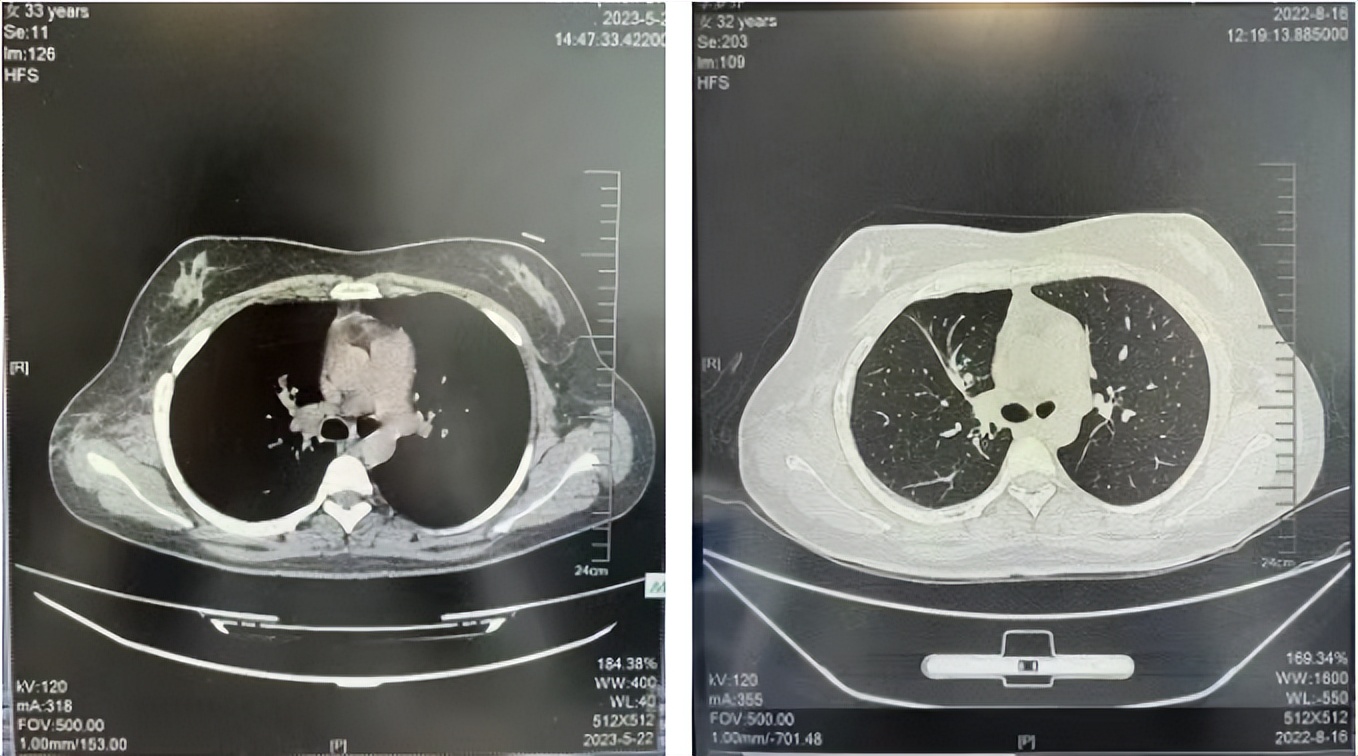

2016年1月复查CT提示支气管截断可见新发小结节,一线治疗采用培美曲塞+DDP方案化疗4周期(培美曲塞3.36,DDP 480mg)。化疗后复查胸部CT:右肺见不规则结节样影,最大层面大小约19mm*8mm,较前比较明显增大,疗效评估PD。2017.3-2017.4予单药多西他赛化疗3周期,疗效评估SD。2018年5月末复查CT提示结节较前增大,评效为PD,2018年6-10月予多西他赛+CBP化疗4周期,疗效评估SD。2022年5月患者出现活动后气短,复查胸部CT示右肺膨胀不良;右侧胸腔积液增多。胸腔积液包埋病理示符合肺腺癌细胞。行NGS基因检测:EML4:exon13-ALK:exon20融合。PD-L1(克隆号22C3)TPS<1%。

临床诊断:右肺上叶恶性肿瘤rT0N0M1a IVA期(第9版分期);恶性胸腔积液。

诊疗经过:2022年5月始口服克唑替尼3个月,出现肝功能异常(DILI 2级伴临床症状),改用恩沙替尼靶向治疗至今,目前评效为维持PR。恩沙替尼应用期间出现轻度肝功能异常(DILI 1级),对症处理后好转。截止目前PFS 33个月。

2018.07

2022.05

2022.08

2023.05

2024.12